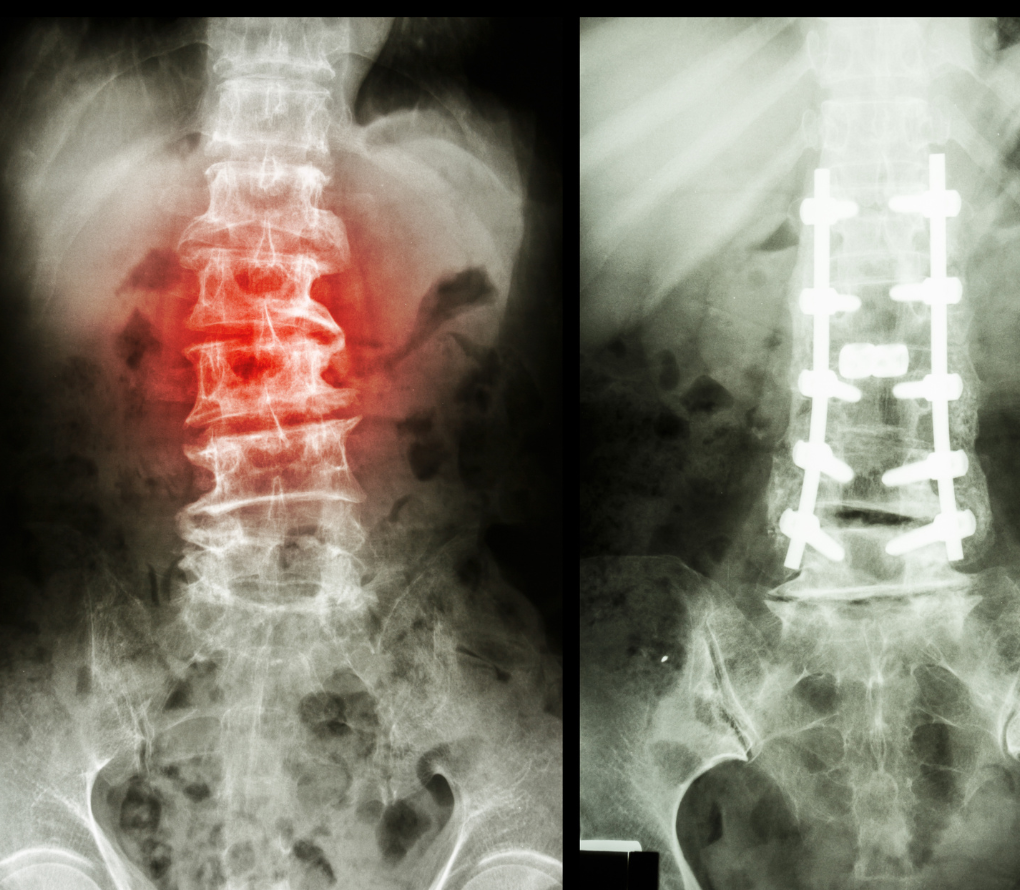

- Decompression surgery (laminectomy/laminotomy): Relieves pressure on the nerves.

- Spinal fusion: Stabilizes the slipped vertebra by fusing it to the bone below.